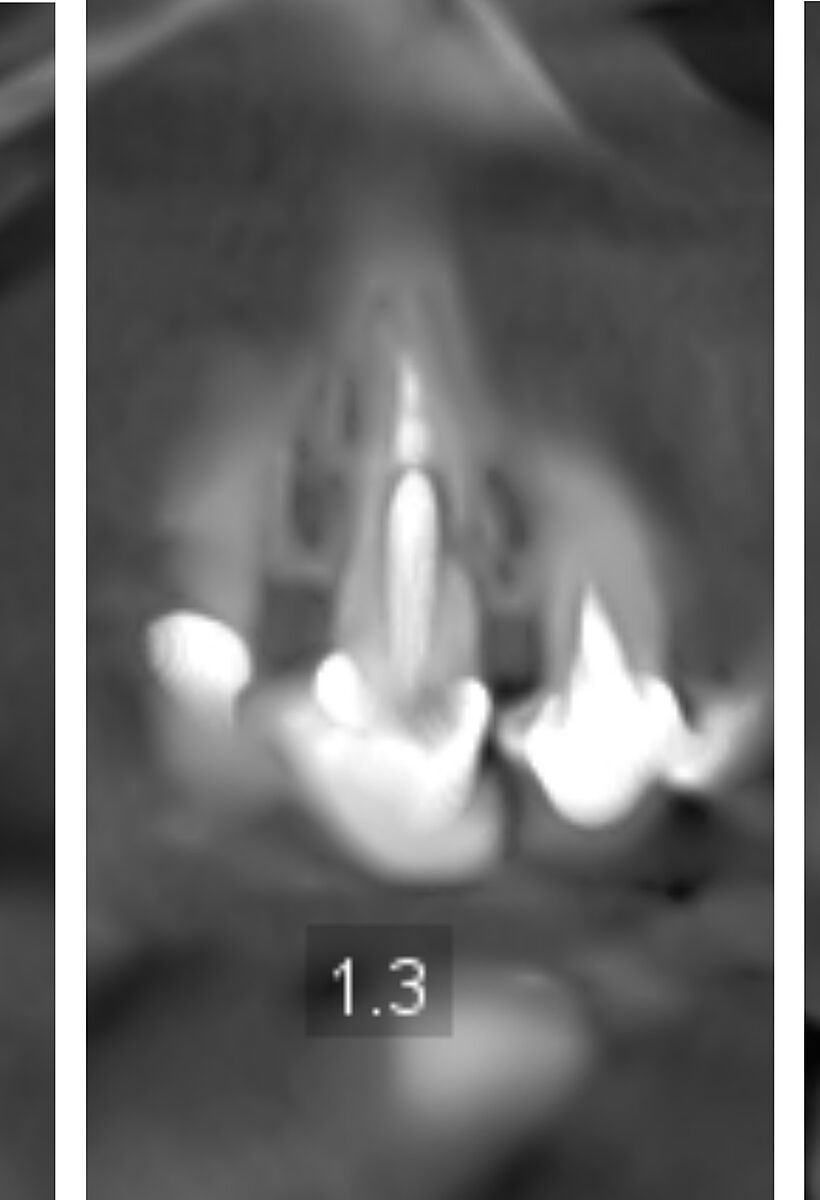

В 70 років приживуться імпланти? Ви суму можете уявити. На знімках канали і корені зубів нормальні, проліковані. Запалень нема. Простіше поміняти старі коронки і поставити незйомні мости на імпланти. По два на одну сторону. Або в такому віці можна дешевий протез, що до ясен прилипає, типу резиновий. Кожні два роки міняти.

Хоч і на штифтах, але корені нормальні, коронка зуба проглядується. У вас навіть прикус правильний при відсутності бокових зубів зверху і знизу. Відстань між щелепами де пусті місця по боках прям ідеально симетричні і не сильно просіли.

Есть здесь зубы нормальные. Есть под вопросом. Т.к. этот снимок надо смотреть полноценно , а не скрины с него. Здесь могут быть и срезы неудачные, и не всегда понятно - артефакты это или на самом деле это есть. + замеры делать надо. И это только рентгенологически... Иногда составляются планы с удалением относительно нормальных зубов для экономии средств и снижения травматичности операции...